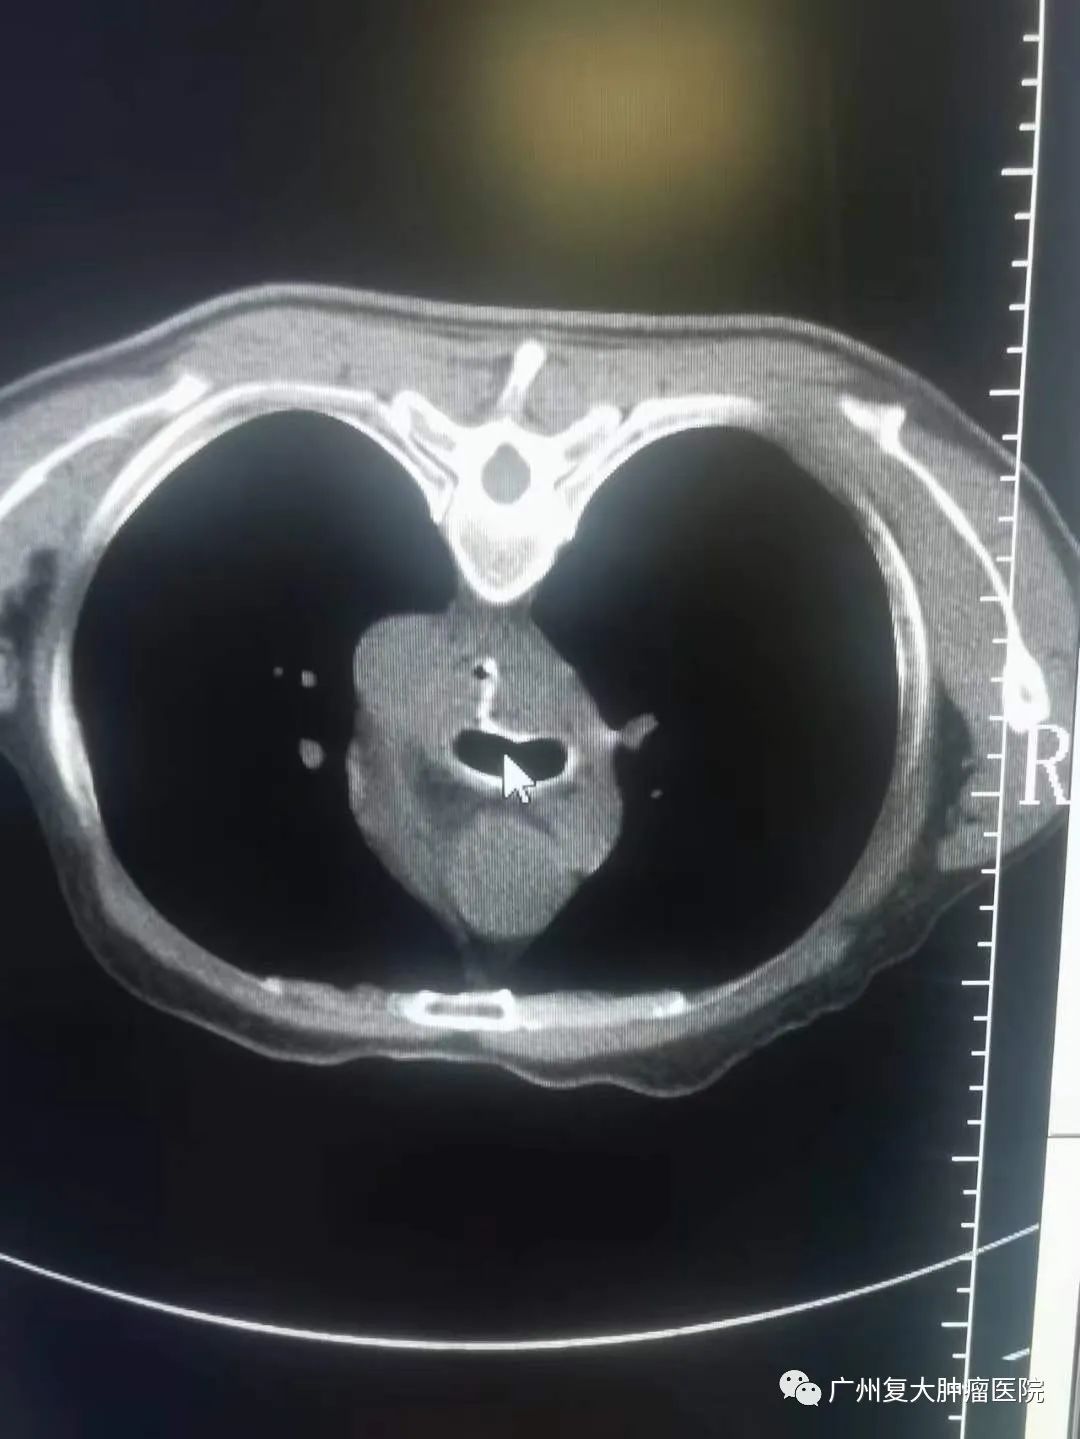

新年伊始,牛立志院长和介入科钟小军医生等医护人员在查房的过程中,收到一名食道癌患者满满的祝福。患者因食道癌并食道-气管瘘在多家大医院寻医问诊,但因带胃管两个多月,进食困难,精神萎靡,生活质量较差。为进一步诊疗,于年前28日晚来到我院,并在隔天完善相关检查后接受食道全覆膜支架置入。术后第一天便可以进食水,精神状态也明显好转。恰逢元旦来临,患者在院感受节日氛围的同时,身体状况也愈来愈好,对他们一家人来说,这不仅是最好的新年礼物,也让他们对新的一年充满新希望。为此,患者把自己亲手写的祝福送给医护人员,以表感谢之情。